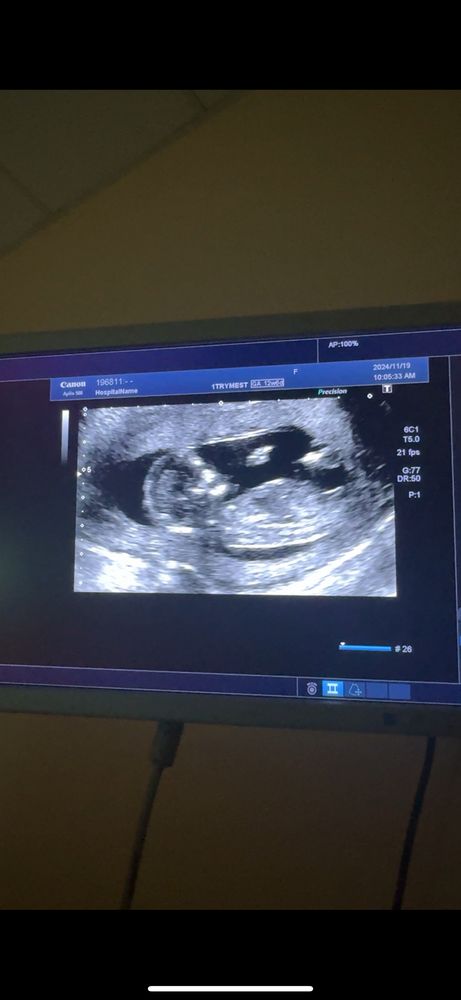

Пол ребенка 1 скрининг

Девочка , угол маленький между спинкой и половым бугорком , почти параллельны. При мальчике большой угол

Девочка, половой бугорок параллельно спинке